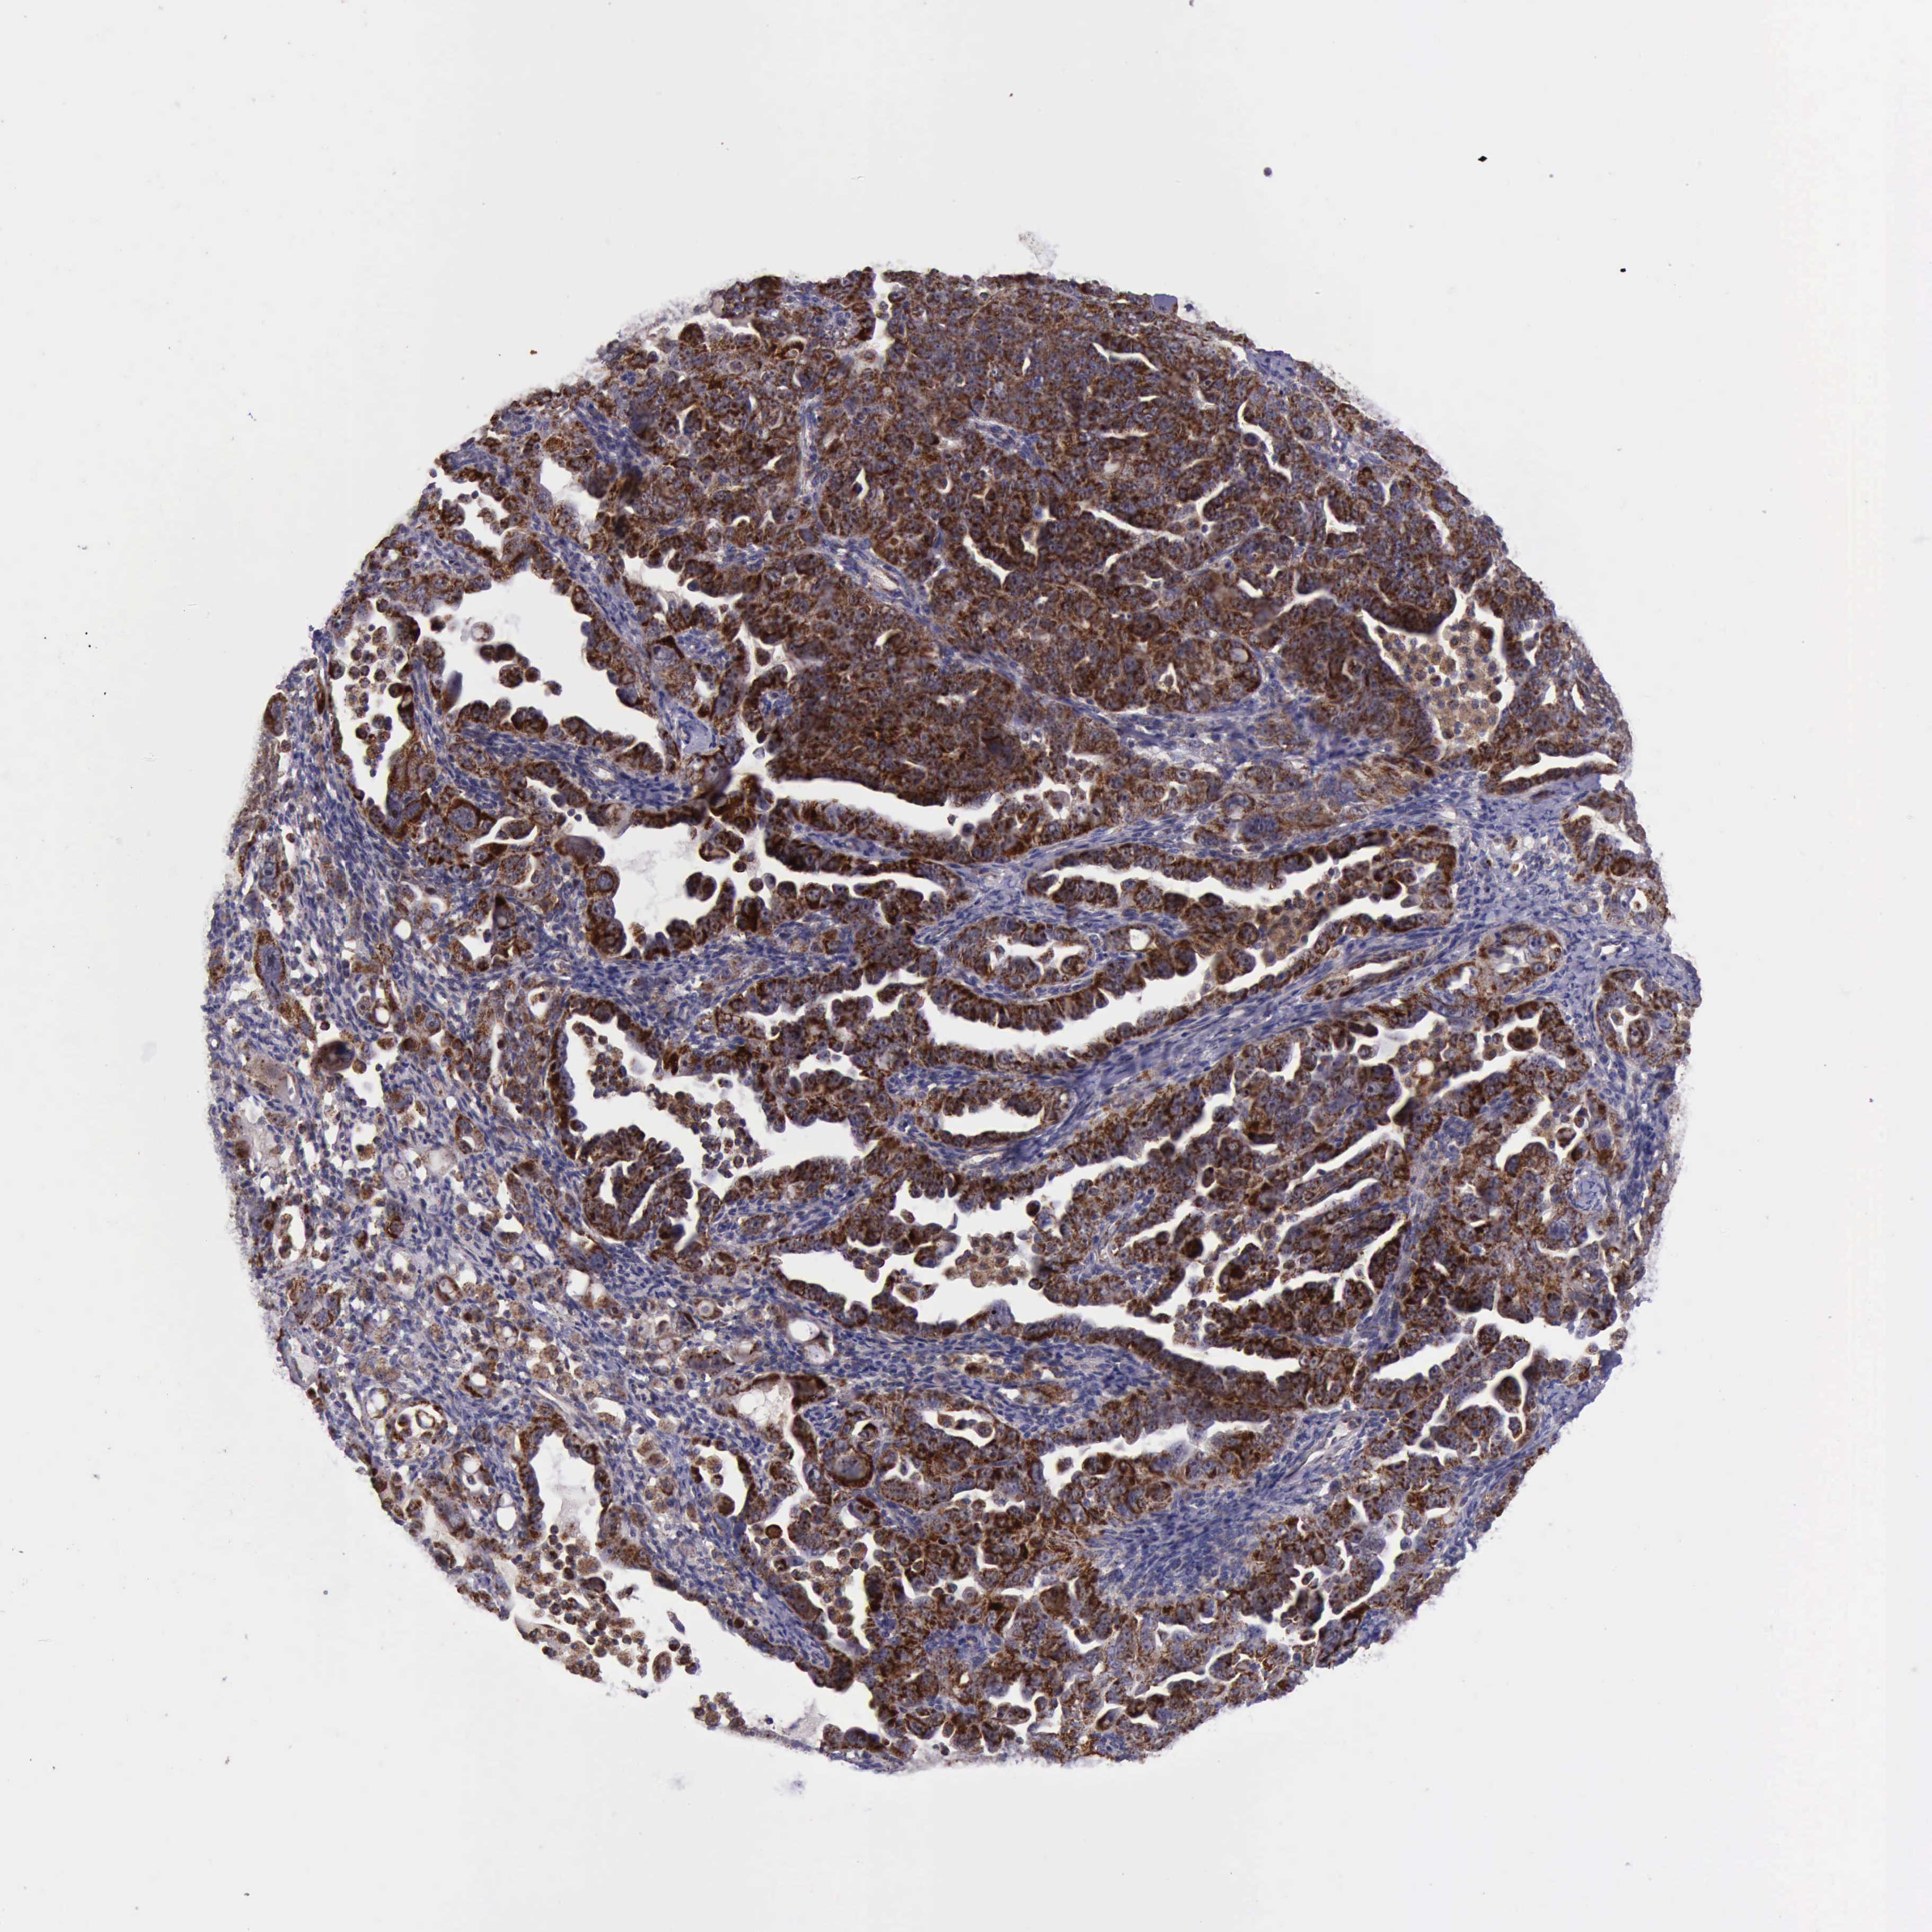

OVARIAN CANCER - Protein expressioni

A mouse-over function shows sample information and annotation data. Click on an image to view it in a full screen mode. Samples can be filtered based on level of antibody staining by selecting one or several of the following categories: high, medium, low and not detected. The assay and annotation is described here.

Note that samples used for immunohistochemistry by the Human Protein Atlas do not correspond to samples in the TCGA dataset.

Antibody stainingi

Antibody staining in the annotated cell types in the current human tissue is reported as not detected, low, medium, or high, based on conventional immunohistochemistry profiling in selected tissues. This score is based on the combination of the staining intensity and fraction of stained cells.

Each image is clickable and will lead to virtual microscopy that enables deeper exploration of all samples and also displays staining intensity scores, fraction scores and subcellular localization as well as patient and tissue information for each sample.

Antibody HPA000994

Antibody CAB008681

Cystadenocarcinoma, mucinous, NOS

Carcinoma, endometroid

Cystadenocarcinoma, serous, NOS

Carcinoma, NOS